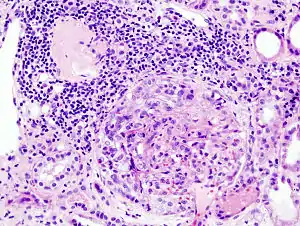

RPGN can be classified into three types, based upon the immunofluorescence patterns:[9]

Type I

Accounting for approximately 20% of RPGN, type I RPGN, also called anti-GBM glomerulonephritis, is characterized by the presence of autoantibodies directed against The antibodies are directed against type IV collagen (specifically, the noncollagenous region of its α3 chain)[5] in the glomerular basement membrane (GBM). Some cases are associated with antibodies directed against the basement membrane of lung alveoli, producing Goodpasture syndrome. The majority of type I disease, however, features anti-GBM antibodies alone; these cases are considered idiopathic.[5]

Type II

Characterized by deposition of immune complexes in glomerular tissues, type II RPGN accounts for 25% of cases. Any immune complex disease—including systemic lupus erythematosus, acute proliferative glomerulonephritis, Henoch–Schönlein purpura, and IgA nephropathy—that involves the glomerulus may progress to RPGN if severe enough.[5]

Type III

Also known as pauci-immune RPGN, type III RPGN accounts for 55% of RPGN and features neither immune complex deposition nor anti-GBM antibodies. Instead, the glomeruli are damaged in an undefined manner, perhaps through the activation of neutrophils in response to ANCA. Type III RPGN may be isolated to the glomerulus (primary, or idiopathic) or associated with a systemic disease (secondary). In most cases of the latter, the systemic disease is an ANCA-associated vasculitis such as granulomatosis with polyangiitis, microscopic polyangiitis or eosinophilic granulomatosis with polyangiitis.[5]